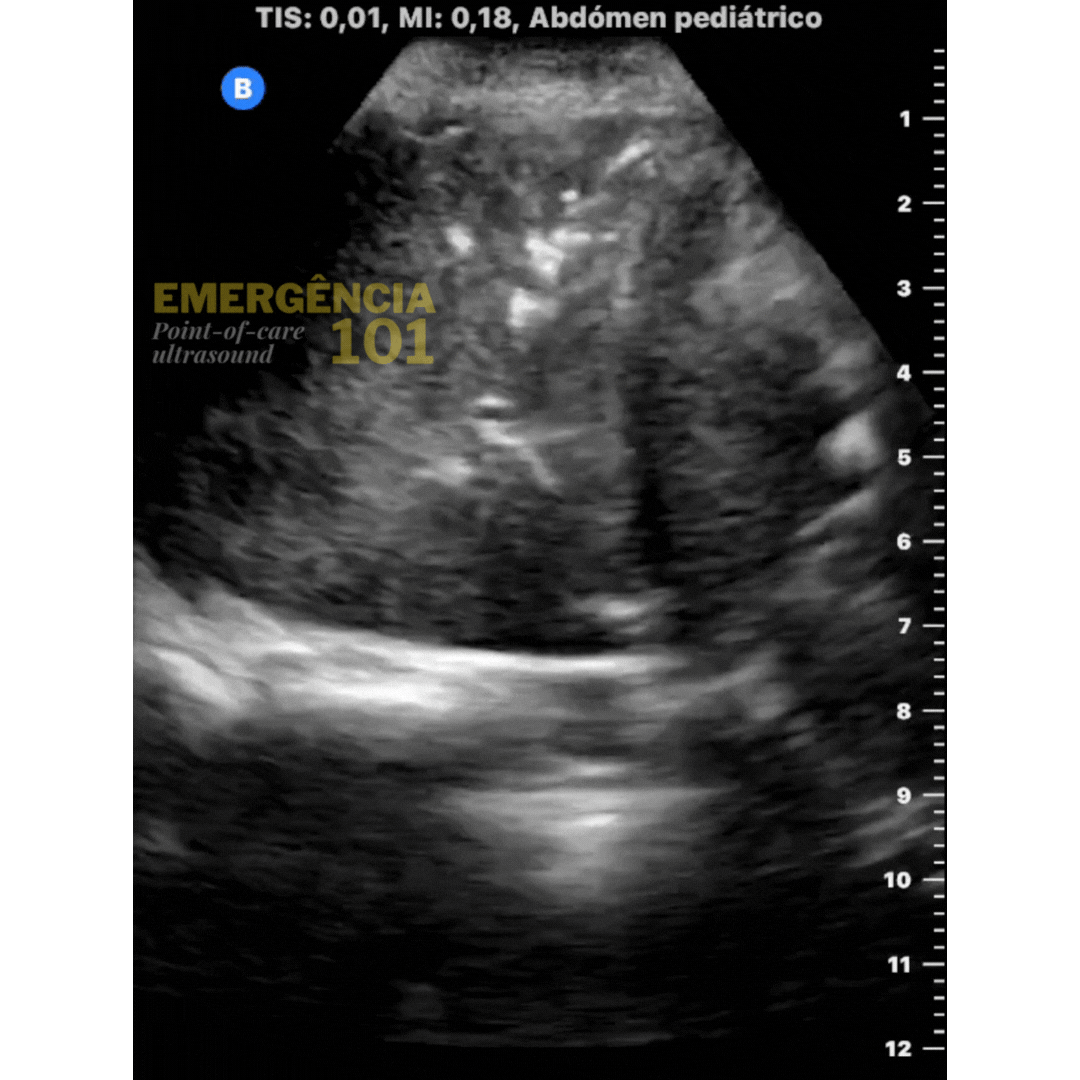

Figura 6a. Hepatização pulmonar em paciente pediátrico, com presença de broncogramas aéreos dinâmicos —representados por essa imagem hiperecóica (branca) dentro do parênquima pulmonar — que se movem com a respiração do paciente. Acervo pessoal do autor.

Figura 6b. Hepatização pulmonar em paciente pediátrico, com presença de broncogramas aéreos estáticos — sem movimento — dentro do parênquima pulmonar. Acervo pessoal do autor.